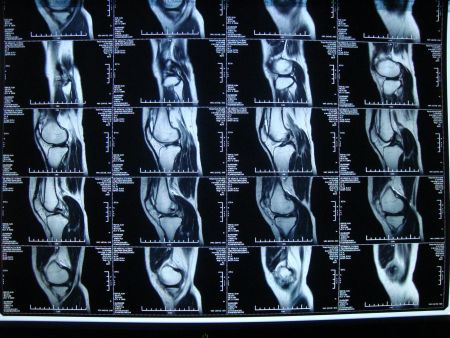

核磁共振是当代生活无法规避的一个课题。经由核磁共振仪这项科学化仪器,人类的身体内部结构迅速神奇的透明化,内部器官的成像高效透露身体的早期病变,医者对症下药,及时维护病人们的生命健康。

人类身体的三分之二由水构成,水又由氢原子和氧原子构成。当我们的肉身暴露在磁核共振仪下,就会引起氢原子的共振反应,通过这样的聚合磁场,人体内部的水分子就会呈现出一定的梯度,从而形成人体内部结构的影像。

核磁共振早先用于癌症、阿兹海默症、帕金森病、脑心肝等的病变诊断,随着技术的流变,它已经适用于身体多类器官的病情处理,根据核磁共振成像,对人体中的大脑、肝脏、胆脾、肾胰腺、肾上腺、子宫、卵巢、前列腺、乳腺、甲状腺淋巴等实质性器官,以及人类的心脏和血管都发挥着不可抹灭的作用。

其中,我们必然提到它对女性乳房器官的病变预警,作为影响女性生命的健康元凶乳腺癌,核磁共振检测可以摸索出癌症病灶的迁徙痕迹,对乳腺病情进行精确性筛查。此外,它还可以对三高人群未来身体隐患做详细的病情预警,以此避免心脏病、糖尿病、心梗、脑梗等疾病的侵袭,在骨髓坏死状态方面的超感反应能力也堪称一流。